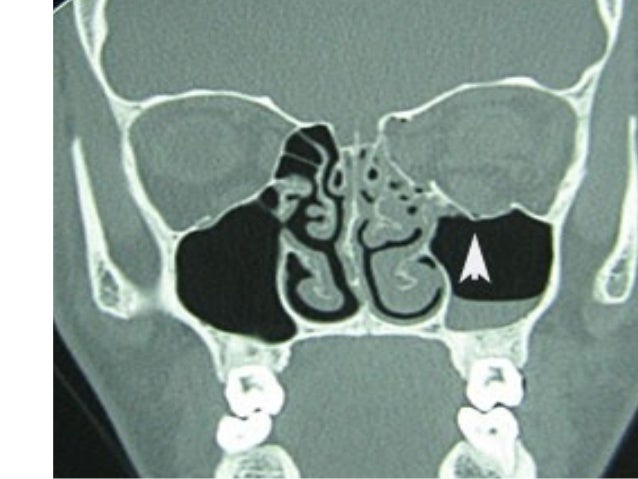

The incidence and causes of maxillofacial trauma and facial fractures vary widely in different regions of the world due to social, economic and cultural consequences, awareness of traffic regulations and alcohol consumption. Maxillofacial fractures can have various causes, including traffic accidents, falls, assaults and sports injuries. Displacement of the zygomatico-frontal suture.The strong central part of the bone usually remains intact and the force is transmitted to the three buttresses, individually or simultaneously (a 'tripod' fracture) resulting in: The bones are either fractured or dislocated. The malar complex is also commonly fractured in isolation by a blow to that area. The most common orbital injury is a 'blowout' fracture, usually involving the orbital floor ± the medial wall.